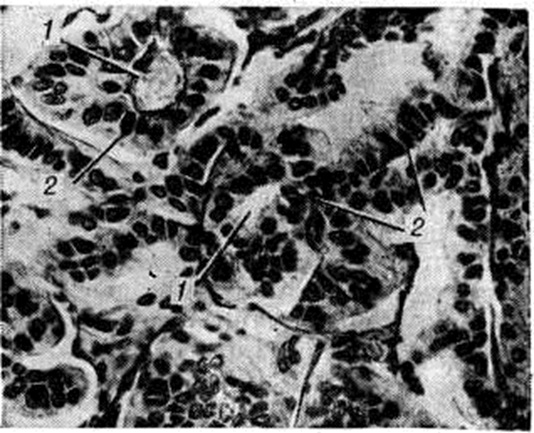

Микропрепарат хориоидпапилломы. Опухоль состоит из ворсинок (1) (на рисунке в поперечном сечении), покрытых цилиндрическим эпителием (2).

Микроскопически опухоль представлена разной величины и формы ворсинками, покрытыми цилиндрическим эпителием, сходным с эпителием нормального сосудистого сплетения (смотри рисунок). Изредка отмечается многослойное расположение опухолевых клеток. Строма ворсинок состоит из рыхлой соединительной ткани, окружающей тонкостенные сосуды. В некоторых ворсинках может обнаруживаться плотная соединительная ткань со значительным числом тонко и толстостенных, иногда спавшихся сосудов. В строме ворсинок возможны отложения солей кальция, гиалиноз, отёк, фиброз и другие